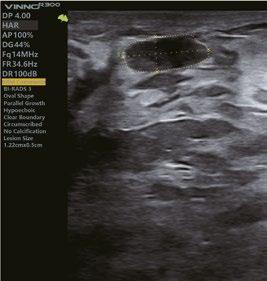

Intelligente Erfassung und Stadieneinteilung von Brustkrankheiten

Das automatische Brustscreening und die Erkennung von Läsionen in Echtzeit oder auf gespeicherten Bildern verbessert zusammen mit der intelligenten Bl-RADSAnalyse die Qualität der Kontrolle nachhaltig.